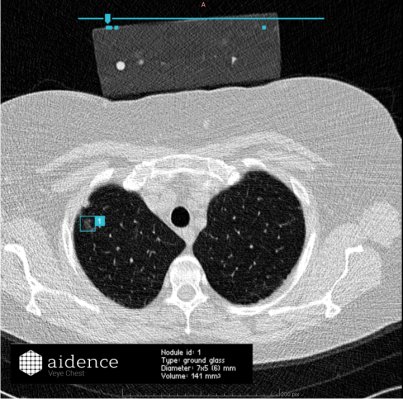

Kliiniseen käyttöön hyväksyttyjen tekoälyä hyödyntävien kuva-analyysien ominaisuudet ovat vielä rajalliset, mutta tietyissä käyttötapauksissa analyysit tarjoavat jo merkittävää lisäarvoa. Suurin osa nykyisistä ratkaisuista on kehitetty tunnistamaan yksittäiseen sairauteen liittyviä löydöksiä yhden kehon alueen kuvantamistutkimuksessa. Esimerkiksi keuhkojen tietokonetomografiakuvista kone voi automaattisesti tunnistaa, merkitä ja mitata kyhmyt, jotka ovat mahdollisesti pahanlaatuisia kasvaimia.

Kuva 2: Konenäkö on merkinnyt ja myös mitannut noduulin potilaan keuhkokuvista

Tarkastellaanpa esimerkkiratkaisuja hoidon laadun ja tuottavuuden kannalta. Keuhkokasvaimia tunnistava ja mittaava analyysi mahdollistaa diagnostiikan laadun parantumisen avustamalla radiologia pienten noduulien löytämisessä satojen leikekuvien joukosta. Tuottavuuden kasvua edistävät analyysin laskemat volyymimittaukset, joiden tekeminen manuaalisesti useista leikekuvista on työlästä ja aikaa vievää.